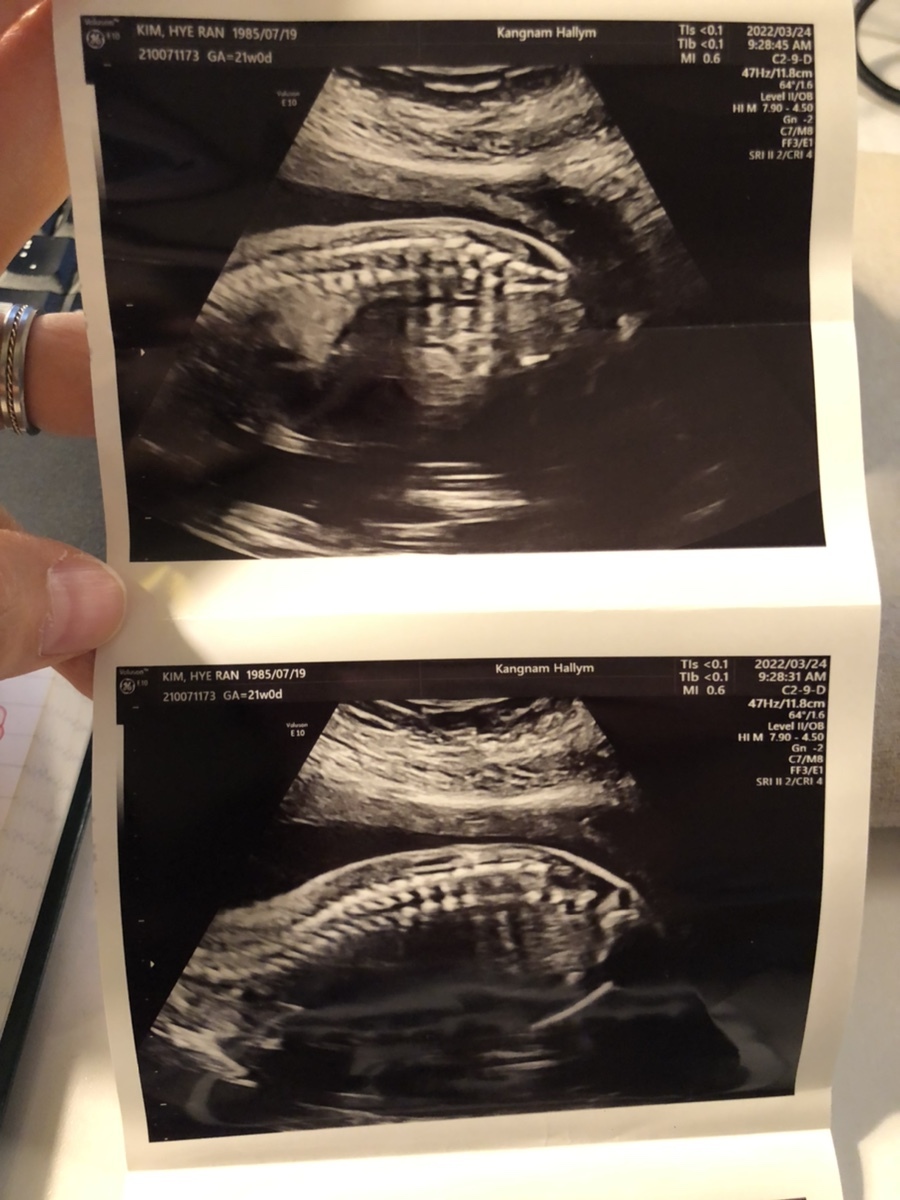

초음파를 보는데 활발하게 뱃속에서 움직이던 이안이, 복부 초음파랑 질 초음파를 볼 때마다 본인 귀찮게 하지 말라는 건지 발길질을 해대는 게 선명하게 초음파 상으로 보인다. 이제 3주 뒤 임당 검사를 준비해 볼까나~